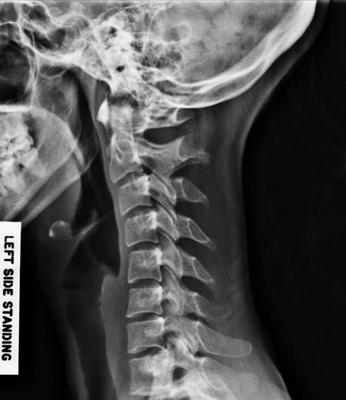

Firstly your cervical spine has a sharp kyphosis; clearly you've had a nasty whiplash with tearing of ligaments, and probable injury to the desk.

Your lumbar spine has an anomaly called a lumbarisation - six vertebrae instead of five. What is good is that the L6 appears well nested, but there are accessory joints visible, all likely to cause pain periodically.

And thirdly there's a suggestion of a short leg giving you a significant curvature; that's where I would suggest you start, though how much and whether it should be a full inner or just under the heel is a decision that needs to be made.